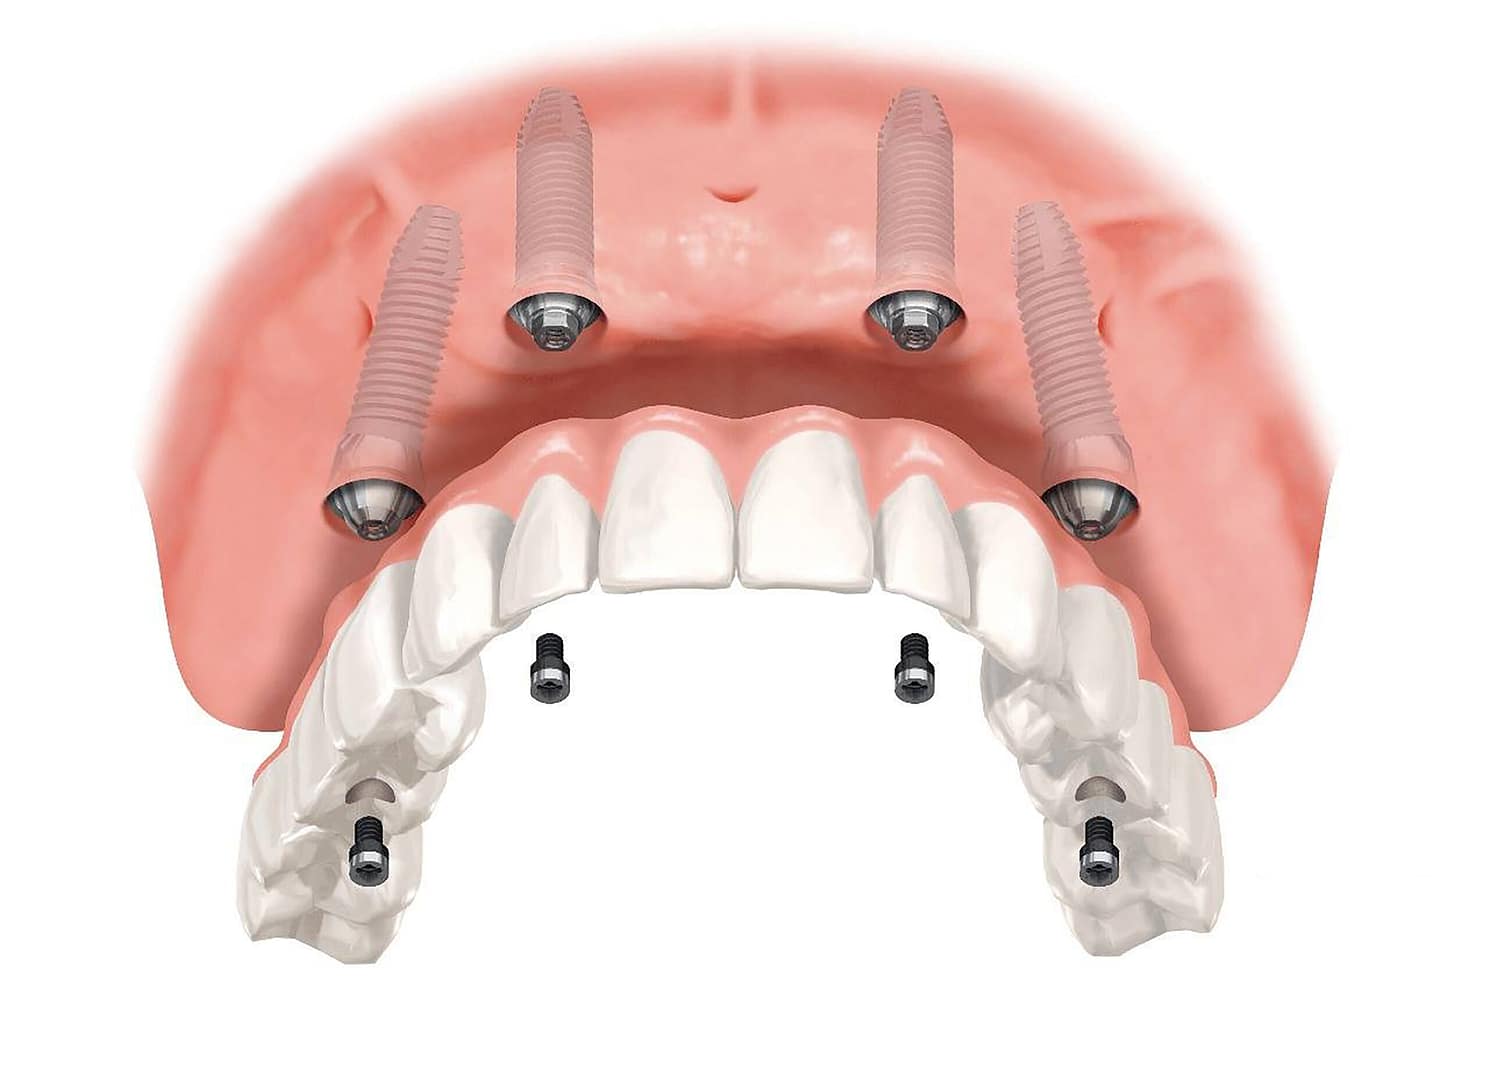

Los implantes cigomáticos son implantes de titanio que son significativamente más largos que los implantes convencionales (pueden medir entre 30 mm y 52.5 mm).

A diferencia de los implantes tradicionales, que se anclan en el hueso alveolar maxilar (el hueso donde estaban los dientes), los implantes cigomáticos se extienden y se fijan en el Hueso Cigomático (o Pómulo).

El hueso cigomático es una estructura densa y fuerte que nunca se reabsorbe, sin importar cuánto tiempo haya pasado desde la pérdida de los dientes.

Los implantes cigomáticos son implantes de titanio que son significativamente más largos que los implantes convencionales (pueden medir entre 30 mm y 52.5 mm).